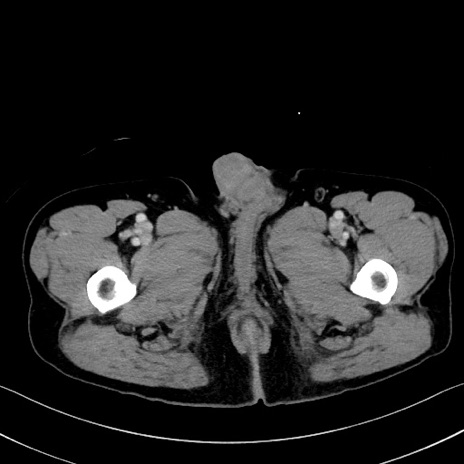

症例35(横断像)

【症例】70歳代 男性

【主訴】腹部膨満、嘔吐

【現病歴】昨日より腹部膨満感出現。本日増悪し、仙痛出現。嘔吐あり、受診。

【既往歴】糖尿病、胆摘後

【身体所見】BP 149/80mmHg、HR 74/min、BT 35.9℃、腹部:膨満、軟、圧痛なし。腸雑音減弱あり。上腹部正中切開瘢痕あり。

【データ】WBC 13500、CRP 1.72